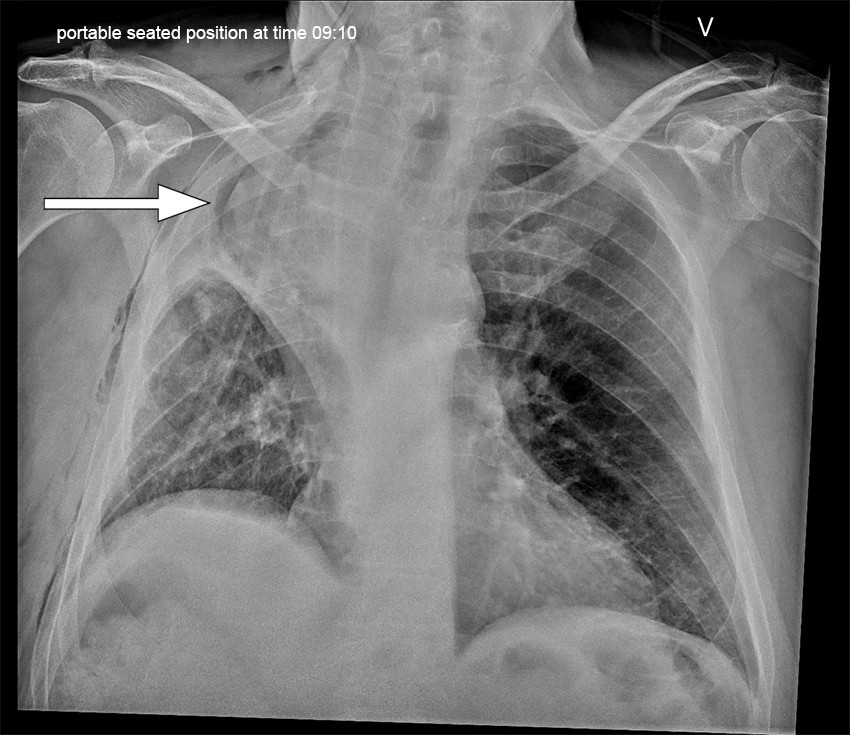

A routine postoperative chest X-ray (CXR) demonstrated opacities typical of atelectasis in the right middle lobe. There was also a small right-sided pneumothorax and small ipsilateral pleural effusion, which is to be expected following surgery. A follow-up CXR on postoperative day 1 revealed increasing opacities in the right upper zone, which might indicate worsening atelectasis, pleural effusion or haemothorax (Figure 1). The patient was not in respiratory distress and had adequate capillary oxygen saturation of 96–98 % with oxygen supplementation of 2 L/min through a nasal cannula. There were no clinical signs of infection.

Mucus plugging was suspected to be causing atelectasis, and therefore bronchoscopy was performed under sedation on postoperative day 1. The middle lobe bronchus was uninspectable because of sharp cranial deviation, although the ostium was unobstructed. The right lower lobe bronchus was open without an abnormal amount of mucus. The patient was consequently treated with non-invasive ventilatory support (NIV) in the form of continuous positive airway pressure (CPAP).